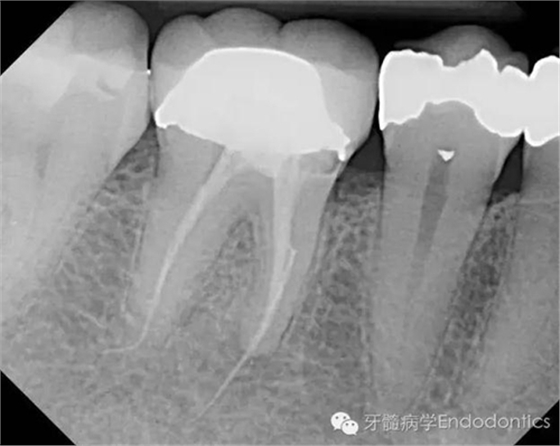

患者因右下第一前磨牙劇烈疼痛、腫脹來診,自訴2年前該牙行根管治療,突發(fā)劇痛。X線示患牙已行根管治療并超填。患牙診斷為已行根管治療合并急性根尖周膿腫。一些牙醫(yī)和牙髓病??瓶赡軙苯硬扇「馐中g治療患牙,而我認為手術是最終手段,尤其對于該病例。

圖1.術前X線片(a)